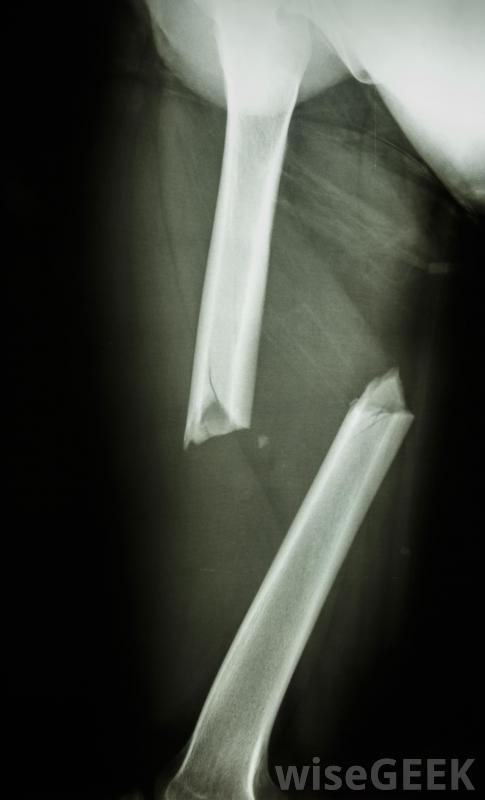

跌倒可能导致三踝骨折如果在检查可能骨折的踝关节时发现这些症状,可能会怀疑骨折。然后可以进行X光检查,以提供准确的诊断。在某些情况下,只有内踝或外踝可能骨折。如果骨骼不太远,骨折被认为是稳定的,这意味着骨折会继续存在当骨头重新排列时,可能不需要手术,治疗可能包括石膏或夹板。如果是三踝骨折或双踝骨折,内踝和外踝骨折,则损伤通常不稳定,通常需要手术

通常会对骨折进行X光检查三踝骨折的外科治疗通常包括使用金属板和螺钉或金属丝将骨折固定在一起鞋子有助于防止许多三踝骨折。